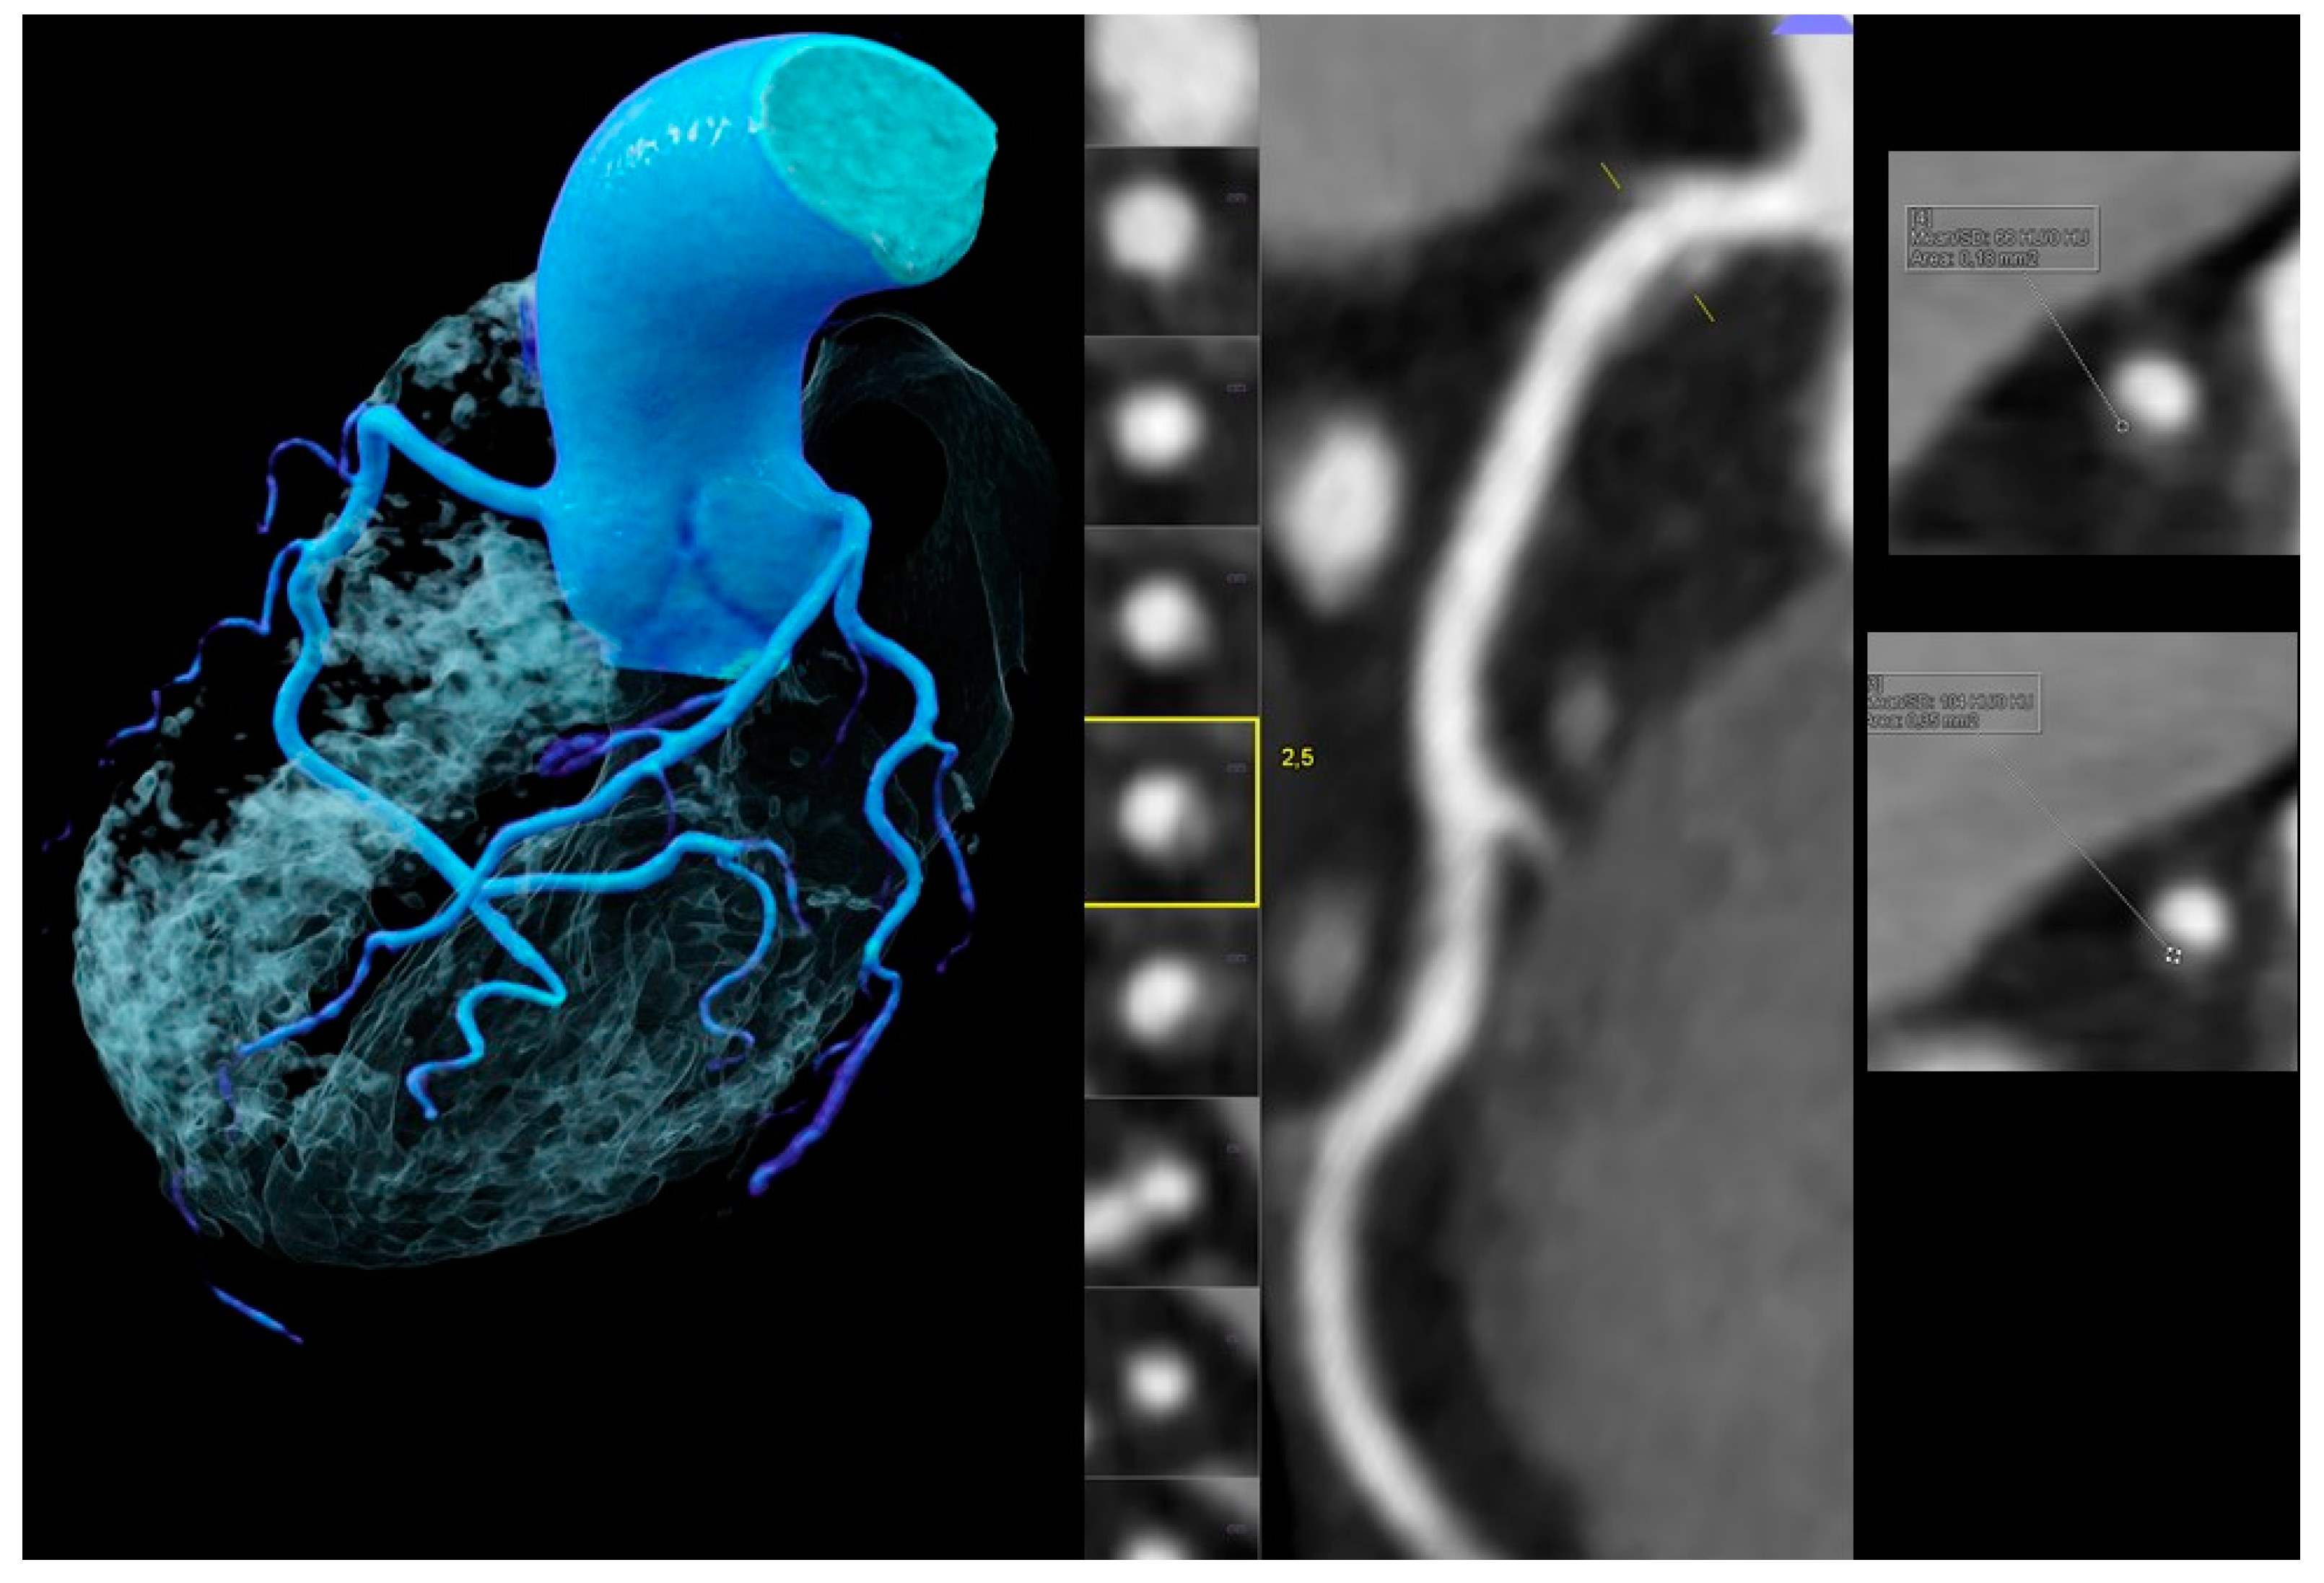

- Low-attenuation plaque (LAP) was defined as a hypoattenuating lesion with <150 HU [25]. CT density was screened with the “pixel lens” and the lowest HU recorded [9]. Then, an area ROI (region of interest) of approximately 2 mm2 size was placed at the region of lowest density and drawn as large as possible, while sparing areas affected by artefacts or adjacent to calcifications, and the CT attenuation (HU) was quantified. If a patient had multiple lesions, the one with the lowest HU was selected for a patient-based analysis. LAP was subdivided into LAP <90 HU, LAP <60 HU (fibrofatty) (11), and LAP <30 HU (lipid-rich necrotic core) [10].